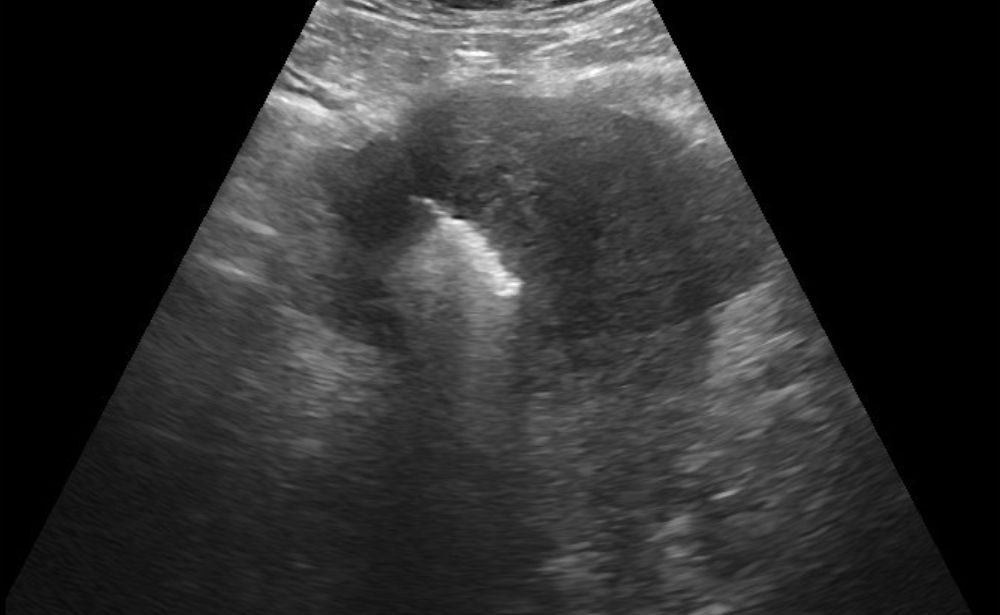

Our Solution: Using ultrasound guidance, a thin probe is placed into the fibroid or adenomyotic tissue. Radiofrequency or Microwave energy safely heats and destroys the targeted tissue.

1. Uterine Fibroid & Adenomyosis Ablation (RFA/MWA)

The Problem: Fibroids and adenomyosis can cause heavy, painful periods, pelvic pressure, and can impact fertility.